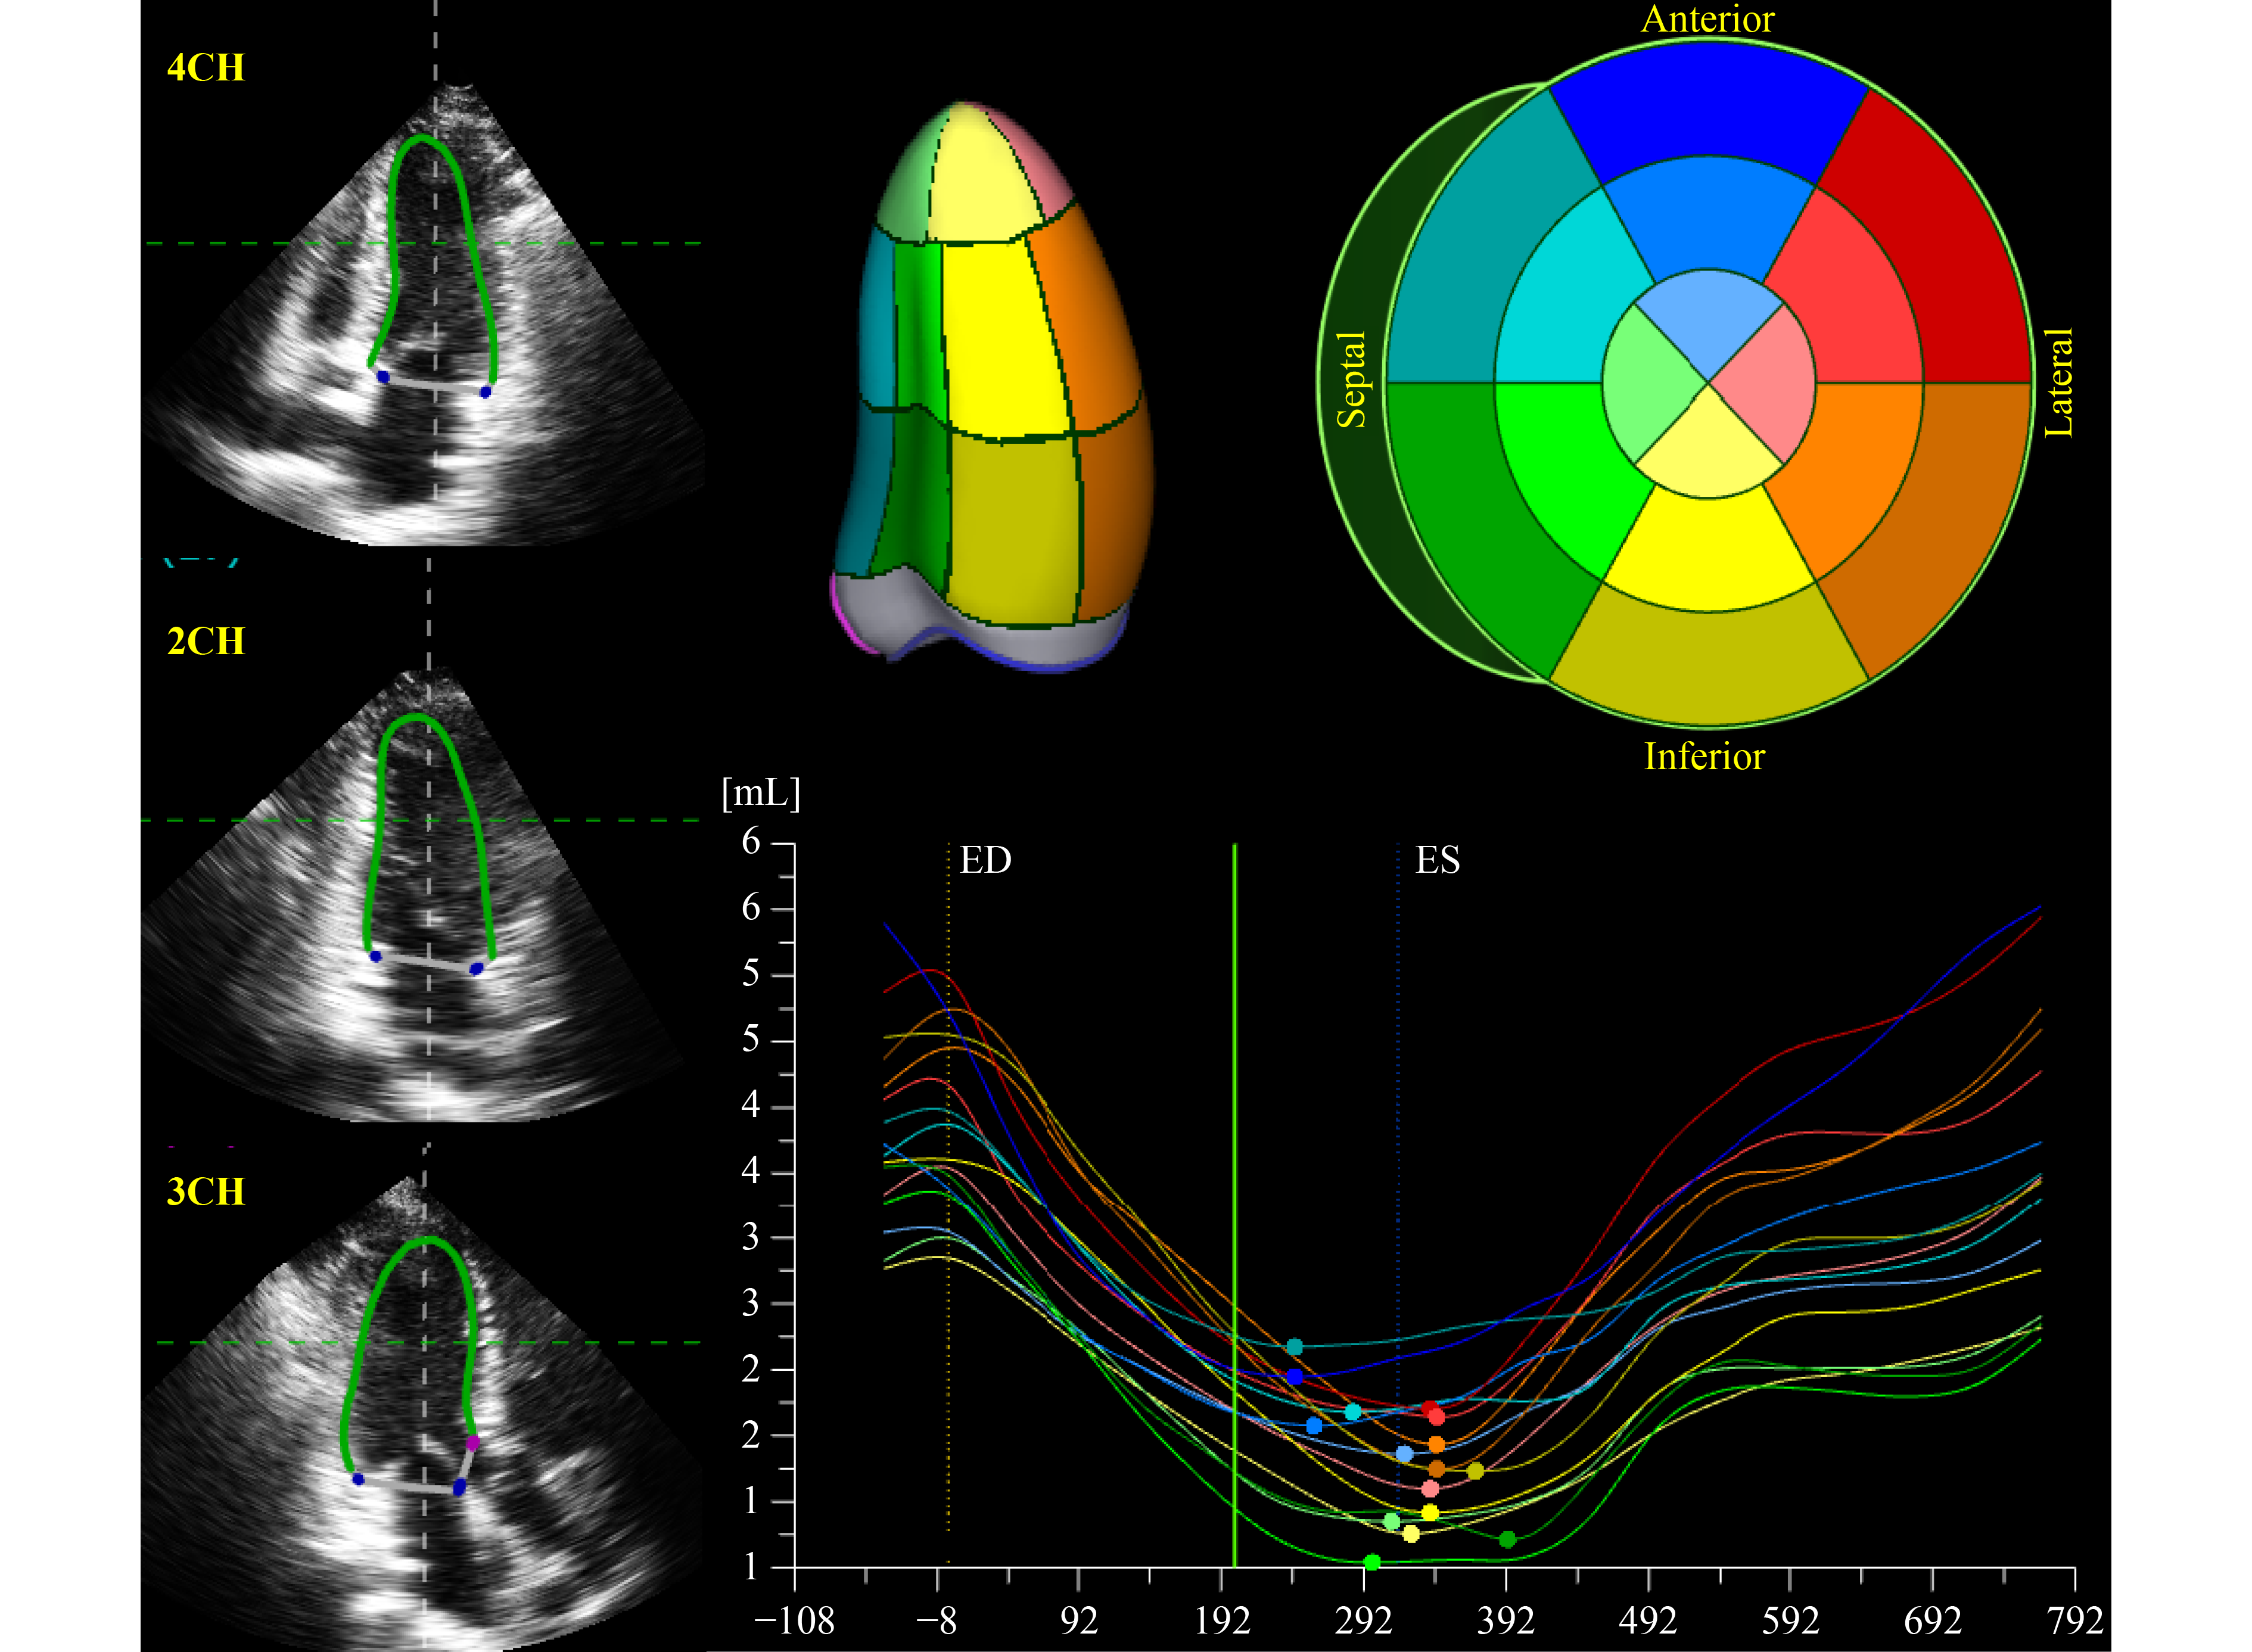

Current guidelines encourage large studies in a diverse population to establish normal reference ranges for three-dimensional (3D) echocardiography for different ethnic groups. This study was designed to establish the normal values of 3D-left ventricular (LV) and left atrial (LA) volume and function in a nationwide, population-based cohort of healthy Han Chinese adults. A total of 1117 healthy volunteers aged 18–89 years were enrolled from 28 collaborating laboratories in China. Two sets of 3D echocardiographic instruments were used, and full-volume echocardiographic images were recorded and transmitted to a core laboratory for image analysis with a vendor-independent off-line workstation. Finally, 866 volunteers (mean age of 48.4 years, 402 men) were qualified for final analysis. Most parameters exhibited substantial differences between different sex and age groups, even after indexation by body surface area. The normal ranges of 3D-LV and 3D-LA volume and function differed from those recommended by the American Society of Echocardiography and the European Association of Cardiovascular Imaging guidelines, presented by the World Alliance Societies of Echocardiography (WASE) study, and from the 2D values in the EMINCA study. The normal reference values of 3D echocardiography-derived LV and LA volume and function were established for the first time in healthy Han Chinese adults. Normal ranges of 3D-LV and 3D-LA echocardiographic measurements stratified with sex, age, and race should be recommended for clinical applications.